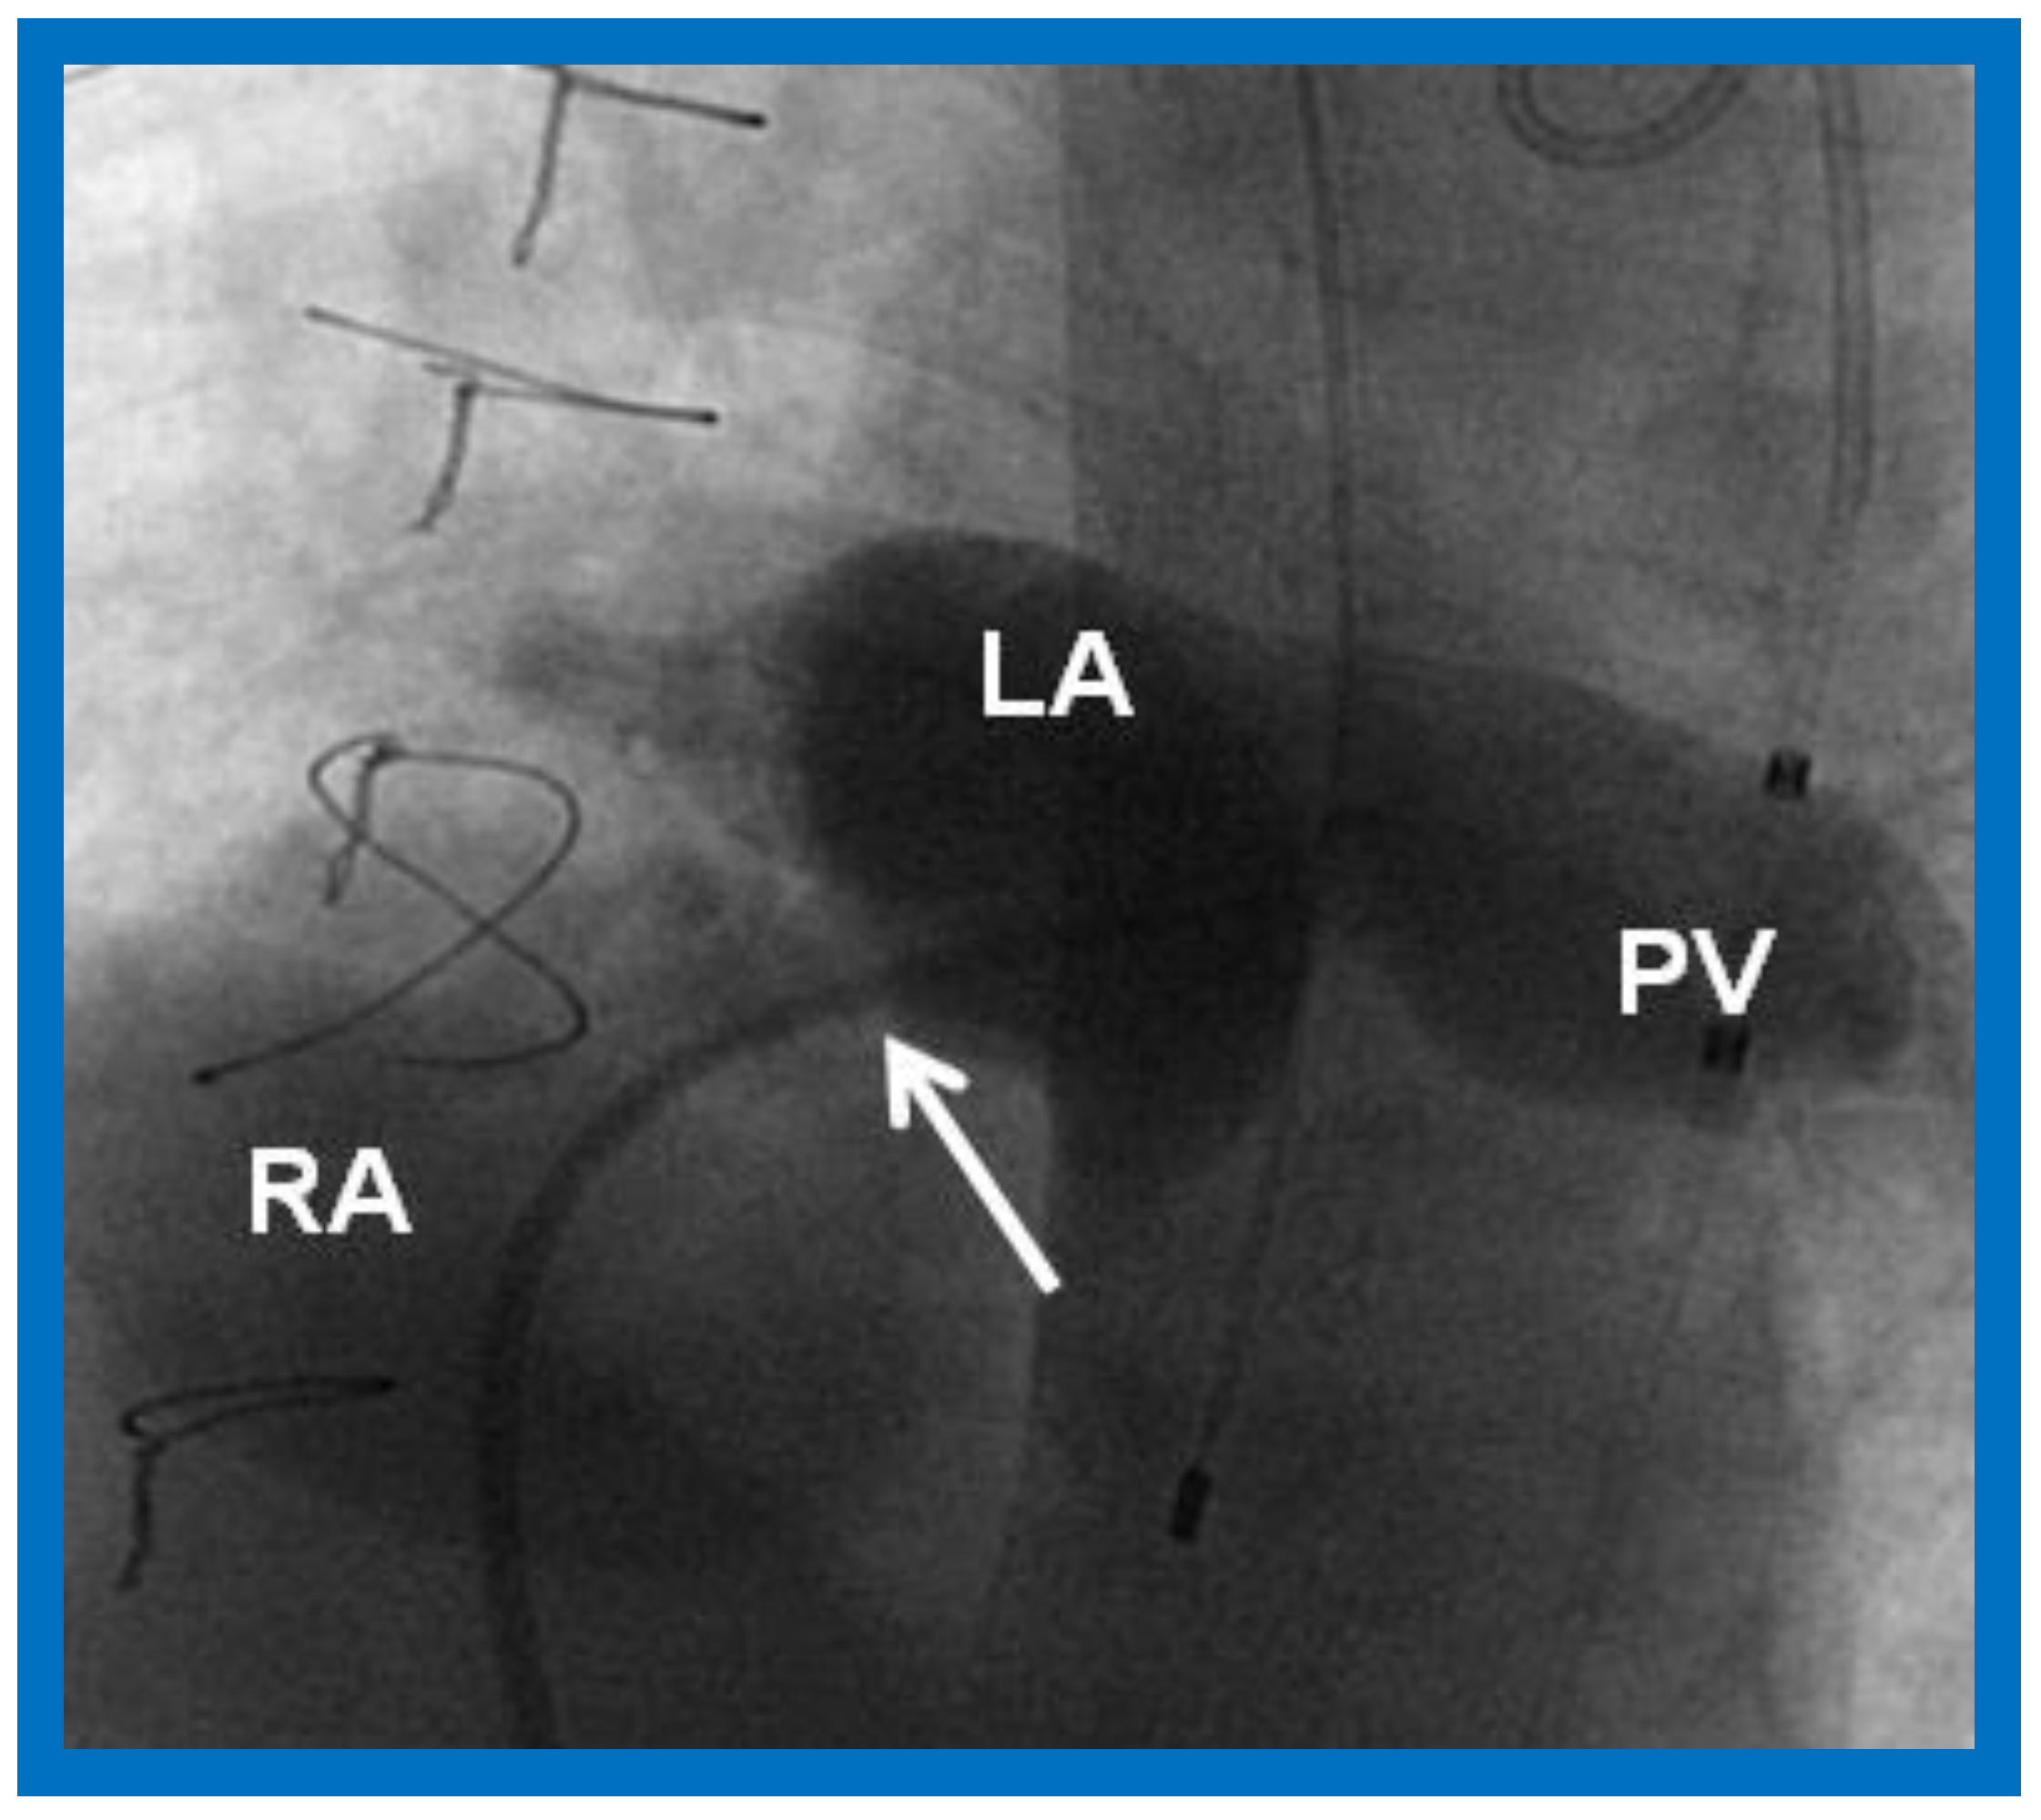

10.1.1. Inter-Atrial Obstruction